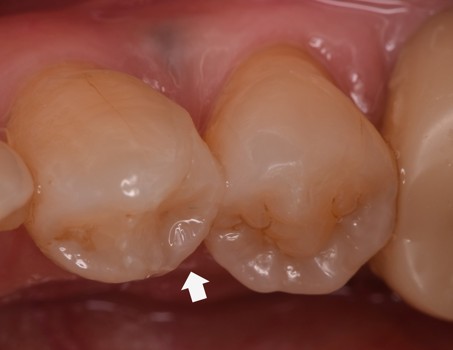

治療前

プラスチックが破損し、内部に2次虫歯ができていました |

虫歯が大きく、深いところまで削ったため次虫歯になってしまうと神経に虫歯菌が感染し神経を取る治療になる可能性が高いため、歯の寿命を延ばすためにダイレクトボンディングを提案させていただきました。 |